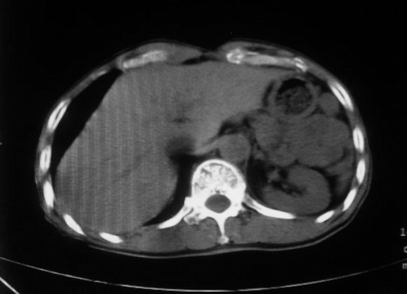

男,66岁,贲门ca术后一年,喝了5、6杯水了。怎么描述跟诊断啊